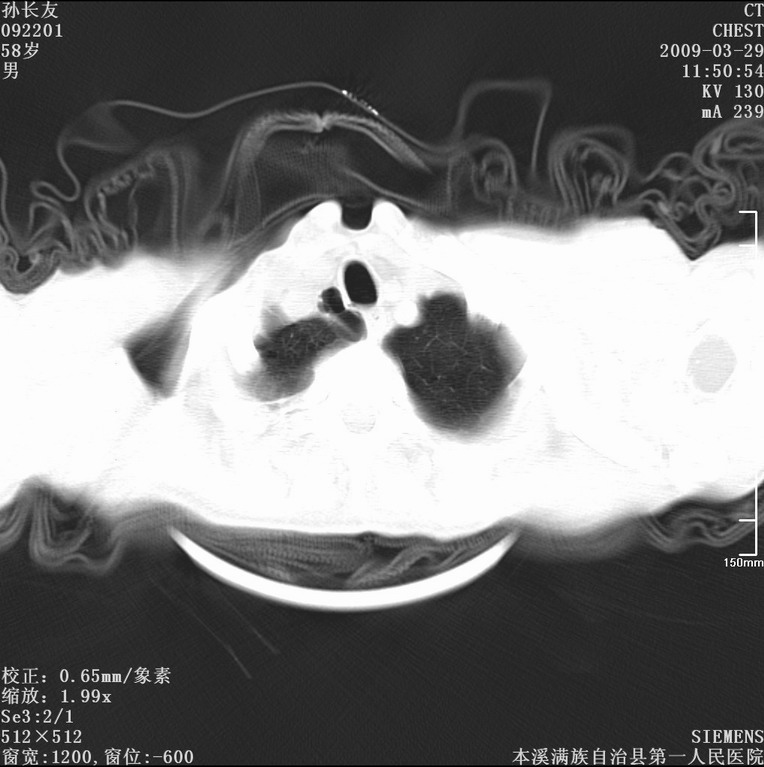

以下是引用liaoqiang在2009-3-30 8:29:00的发言:[br]所上传的层面示气管未见确切异常。